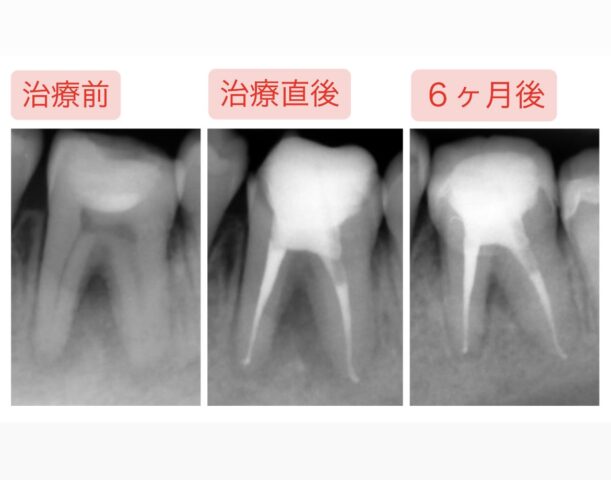

レントゲンを見ていきましょう。

お口全体のパノラマレントゲンでもわかるほど、根っこの先に病変があります。

治療前後のデータをご覧下さい。

病変も縮小し、溶けていた骨も回復しました!